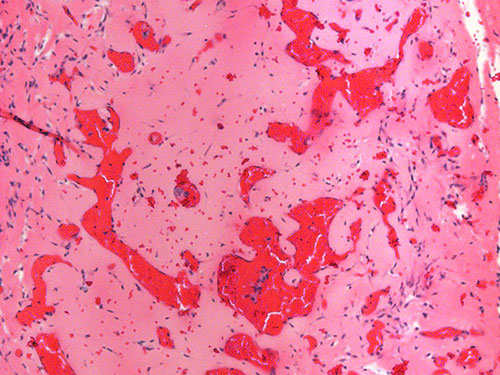

1) Diagnostic biomarker identification and analysis for vascular anomalies

2) Human patient-derived cell xenograft models of vascular anomalies

3) Mouse models of vascular anomalies

“Pathogenesis and Treatment of Kaposiform Lymphangiomatosis“

The major goals of this project are to test the hypothesis that the somatic p.Q61R NRAS mutation in human endothelial cells drives the pathogenesis of KLA and elevated production of ANGPT2.